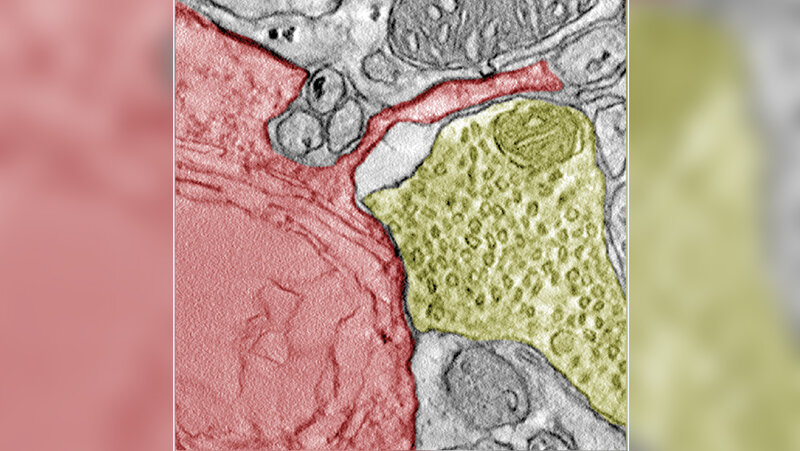

Für ihre Forschung analysierten die Forschenden Daten, durch die sie eine Reihe von Genen identifizierten, die mit der Synapsenbildung in Verbindung stehen. In Zellkulturen und im Mausmodell bestätigte sich die Entdeckung, dass Zellen des kleinzelligen Lungenkrebs funktionale Synapsen mit Neuronen bilden. „Ich war verblüfft, als wir das Ausmaß der Neuronen sahen, die die Krebszellen kapern konnten”, erklärt Seniorautor Professor Dr. Matteo Bergami, Forschungsgruppenleiter am Exzellenzcluster für Alternsforschung CECAD der Universität zu Köln. „Ich glaube, dieses Ergebnis wird die Medikamentenentwicklung transformieren und zu effizienteren Therapien führen, die eine Metastasierung des kleinzelligen Lungenkrebses im Gehirn verhindern.“

Als verantwortliche Neurotransmitter konnten die Forschungsgruppe Glutamat und GABA ausfindig machen. Waren sensorische oder kortikale Neuronen involviert, konnte der Krebs schneller wachsen. Die Zellen zeigten eine hohe Anpassungsfähigkeit zur Beschleunigung des eigenen Wachstums. Die Hemmung von Glutamat führte zur verringerten Tumorlast und die Mäuse konnten länger Überleben – es könnte sich daher als neuer Angriffspunkt für weitere Therapieansätze entpuppen. Diese Form der Therapie ließe sich auch mit einer Chemotherapie kombinieren.